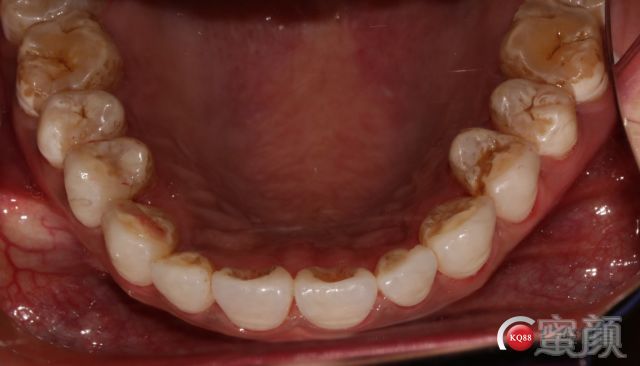

诊断牙模要自己去备牙,千万不能取个模型甩给技师让他凭感觉磨了做;要告知技师你的要求;牙面形态。切端通透性;交流知道技师需要多少空间;在风险可控范围相互平衡。但都要提前做好准备。

下颌我要等技工室的全合架到位了再做;因为涉及到几个合位关系的确定问题;下颌要采用对接式所以侧方合关系要特别注意,不然会出问题。患者很满意;中缝黑三角2周后应该可以恢复;排龈时间压得有点长;两单位对称粘接;邻间隙一定要能过牙线,再往下做;手术刀慢慢刮还是有点费力。效果不错患者满意。